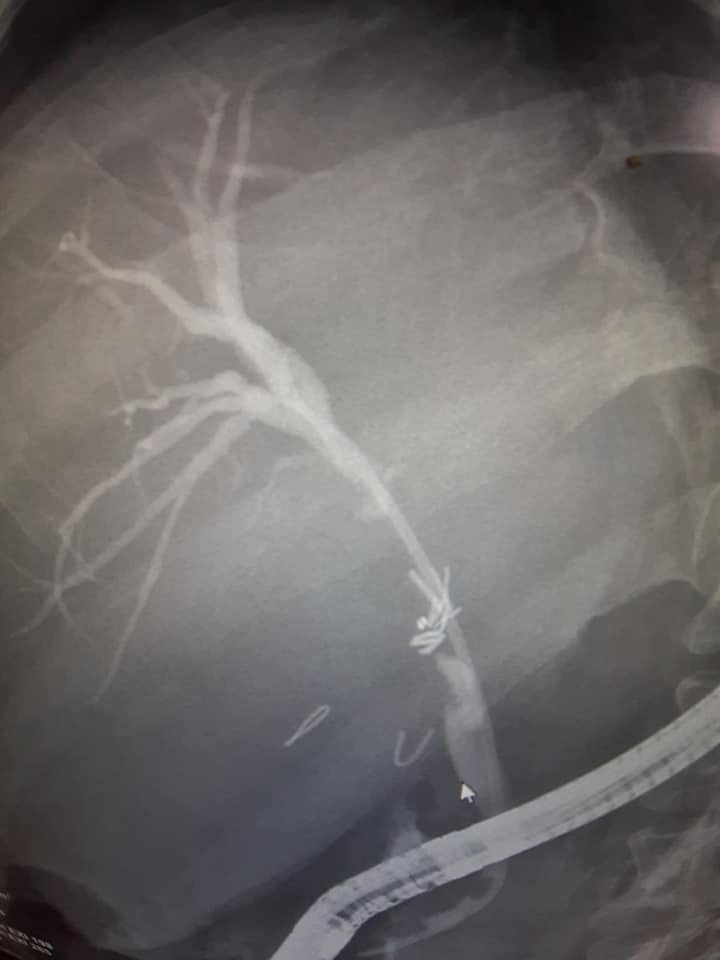

هذه الصور مع مقاطع لفيديو توضح أهمية وطريقة إستخدام مناظير القنوات المرارية لعلاج الصفراء الإنسدادية والتسريب المراري الناتج عن إصابة القناة المرارية ، وبعض هذه الحالات قد تكون حرجة وصعبة مثل هذه الحالة التي تم لها إجراء عملية إستئصال المرارة بالمنظار بمستشفي آخر وتعاني من صفراء انسدادية وتسريب السائل المراري بعد العملية وتم عرضها علينا لعمل المنظار علي القنوات المرارية مع تركيب دعامة وتحتاج مثل هذه الحالات إلى الخبرة والمهارة لإجراء المنظار بطريقة دقيقة وذلك لنجاح إجراء المنظار ووضع دعامة لتصريف السائل المراري والحصول علي أفضل النتائج في مثل هذه الحالات الحرجة والصعبة والتي تحتاج إلى المتابعة المستمرة من الجراح المعالج للحالة وإجراء اللازم والعمليات اللازمة حتي بعد إجراء منظار علي القنوات المرارية مثل عملية توصيل القناة المرارية بالأمعاء الدقيقة أوحسب مايراه الأطباء المتخصصون .

These images and unedited videos demonstrate the value of therapeutic ERCP for treatment of some critical and difficult cases of iatrogenic biliary injury after Laparoscopic cholecystectomy whether the injury is partial or complete cicumferential injury with or without segment loss of the bile duct.

This case was referred to us for therapeutic ERCP for treatment of obstructive jaundice and biliary leak after Laparoscopic cholecystectomy that was done in another hospital.

ERCP was done , and the guide wire was successfully passed to the proximal biliary tree bridging a gap of complete circumferential injury of the upper part of the CBD with lost segment, the guide wire was passed meticulously from the upper end of the divided CBD into a gap of lost segment, then passed in the axis of the distal end of the common hepatic duct for successful bridging and cannulation of the proximal biliary tree and Plastic stenting of the bile duct was done successfully bridging the gap of lost segment with free flow of bile.

This Patient is in need of follow up for evaluation and management . MRCP is of value during follow up and Roux – en Y Hepaticojejunostomy may be necessary for biliary Reconstruction.